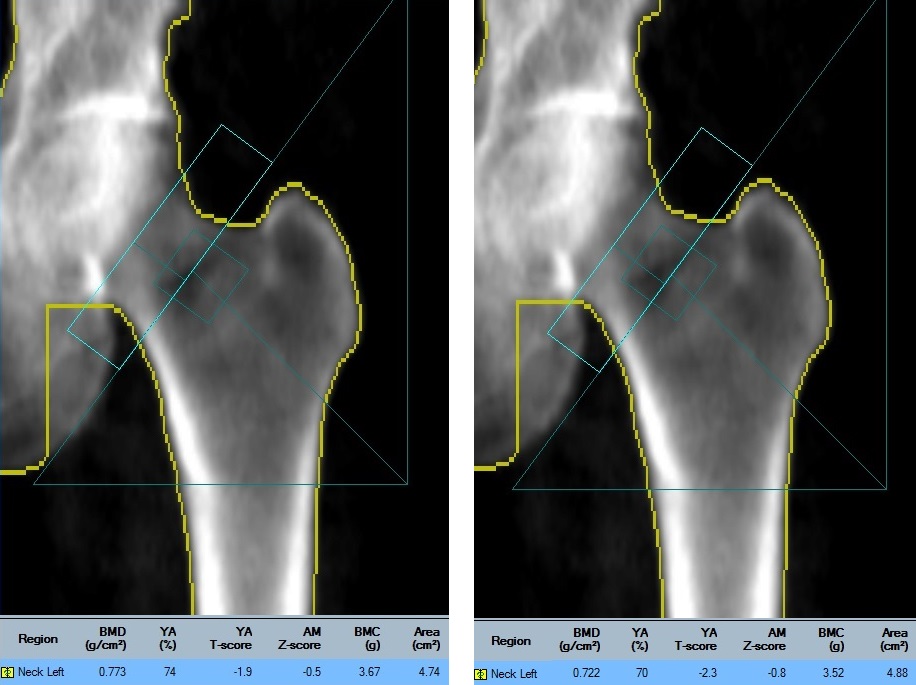

Two different placements of the neck rectangle for the same scan are shown here. When placed over the denser area of the pelvis, the ROI box calculates a falsely elevated the BMD. Excluding the pelvis from the analysis calculates the correct T-score of -2.3.

When a patient has a short femoral neck, the DXA technologist must use caution in placing the femur neck region-of-interest (ROI) rectangle to ensure that it does not overlie the denser area where the pelvis intersects the femur just below the femoral head.

If the neck box includes the denser pelvis bone, the BMD will be falsely elevated. This is something that should be considered when interpreting serial scans. Out of the six numbered femur scans, the most reliable measurements are numbers 1, 2, and 6. When scan 6 is compared to scan 5, there appears to have been a BMD loss that exceeds the LSC for this facility, however this is likely incorrect. Scan 6 is more appropriately compared to numbers 1 and 2 from which there has been no significant change.